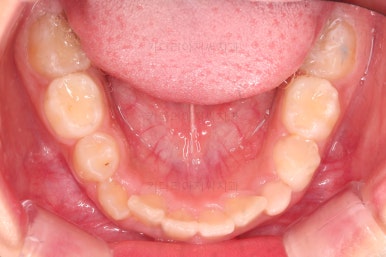

1. 초진

초진 시 입안의 모습입니다.

가장 눈에 띄는 건, 아랫니가 윗니보다 앞에 나와있는 부정교합인데요.